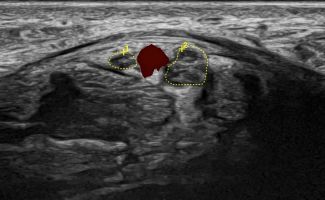

- Entrapment Syndromes (carpal tunnel syndrome, cubital tunnel syndrome, tarsal tunnel syndrome, meralgia paresthetica)

- Focal Lesions (tumors, neuromas)